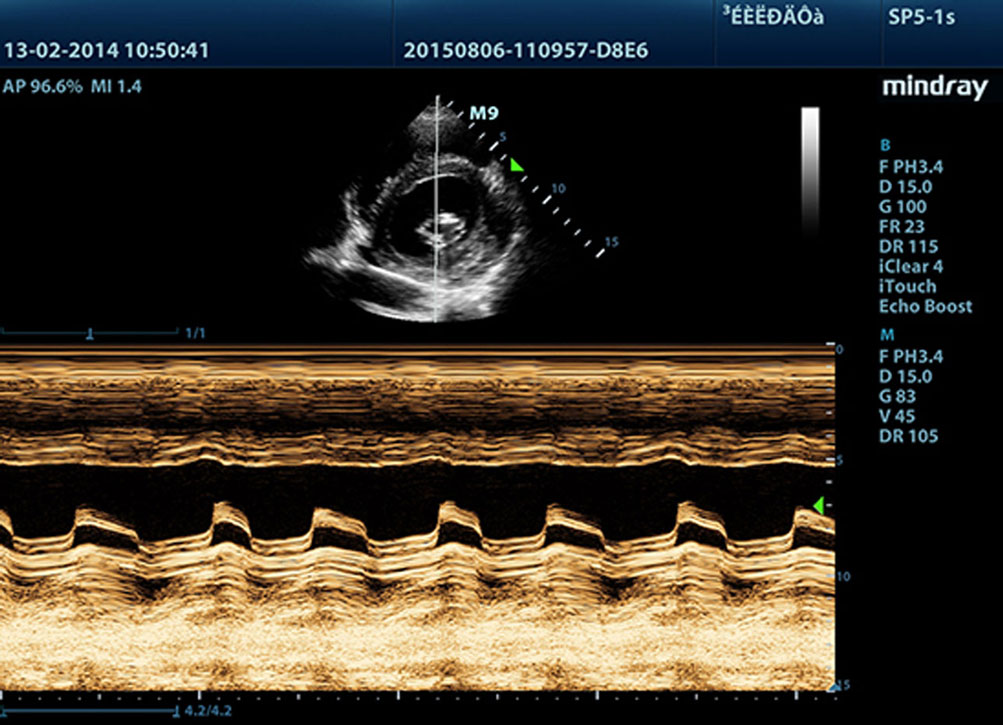

Daha belirgin g?rĂŒntĂŒler sa?layan, M9 ile uyumlu tĂŒm problar Mindray'in benzersiz 3T prob teknolojisiyle teslim edilir. Single crystal teknolojisinin eklenmesiyle gĂŒcĂŒ artan M9, ?zellikle zorlu hasta taramas? s?ras?nda daha iyi penetrasyon ve dinamik renk ak??? olana?? sunar.

?evredeki parazit gĂŒrĂŒltĂŒleri bast?r?rken gĂŒ?sĂŒz eko sinyallerini art?rmak i?in ba??ms?z sinyalden-gĂŒrĂŒltĂŒye bilgisini kullanmak ĂŒzere tasarlanm?? ak?ll? eko tespit ?zelli?i ile Mindray'in benzersiz uyarlanabilir sinyal i?leme teknolojisi, daha dengeli g?rĂŒntĂŒ parlakl??? ve miyokard doku katmanlar?n?n daha iyi g?rĂŒntĂŒlenmesini sa?lar.

Free Xros M?

?rnekleme ?izgilerini herhangi bir a??ya serbest?e yerle?tirerek kesin bir anatomik g?zlemin kazan?lmas?. 3 ?rnekleme ?izgisinin ayn? anda g?rĂŒntĂŒlenmesi sayesinde daha iyi g?rĂŒntĂŒlere ula??lmas?.